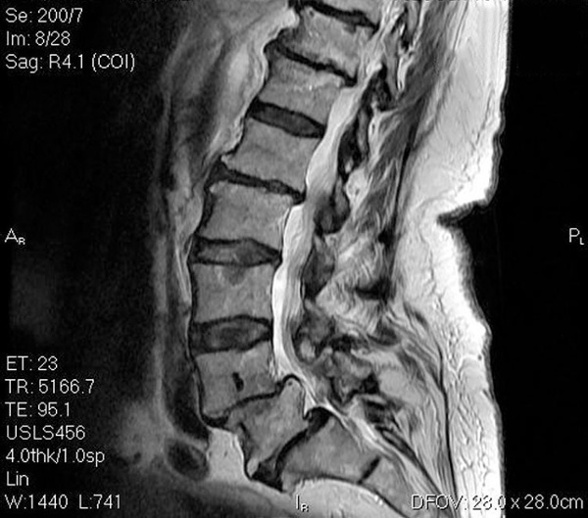

Lumbar Spine Master Class – November 11 – Portland, OR

Ever struggle with which patients are a good candidate for surgery or not? Dr. Laurie McLaughlin, PT, DSc, FCAMPT, CMAG, MCPA has seen A LOT of spine related complaints throughout her career and has done more than 5000 spine surgery consults over the past decade. The Lumbar Spine Master Class will address recognizable patterns of presentation and help PTs identify those not fit for therapy early on and get them to a more appropriate resource, and vice versa.